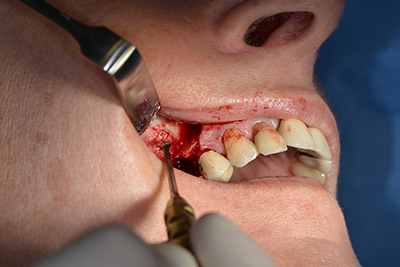

Последващите отвори се изборват с намалени обороти от 300 rpm. Implantmed демонстрира своя истински потенциал на този етап. Хирургичният протокол може да бъде зададен – различните позиции могат да бъдат лесно избрани чрез натискане на позиция “P” на педала (Фиг. 10 и 11).

Следващата програмирана позиция е поставянето на импланта и в нашата практика е предварително настроена на сила 32 Ncm (Фиг. 12).

Следващата стъпка е синус лифт с непосредствено имплантиране. Implantmed е предварително настроен на първа позиция за букална фенестрация на стената на максиларния синус.

Фенестрацията е извършена при 35,000 rpm и след това носната лигавица е обработена по посока на челюстта (Фиг. 13 to 14).